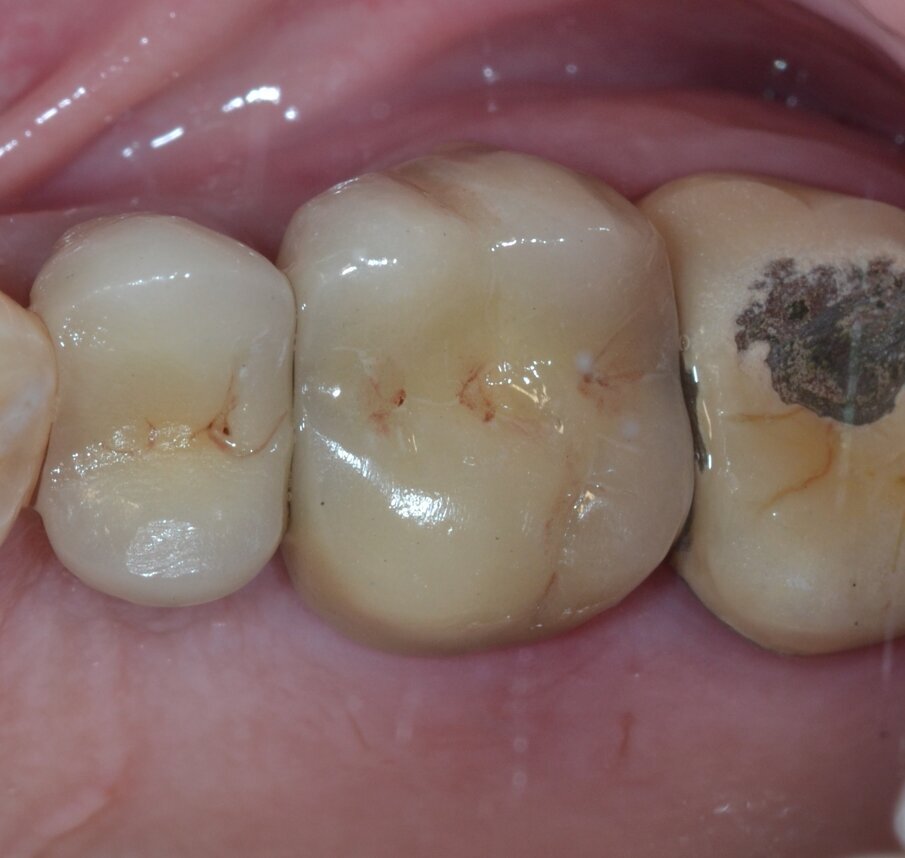

Paziente di aa 56, maschio, giunge alla nostra osservazione lamentando dolorabilità alla palpazione e alla masticazione in corrispondenza dell’elemento 1.6 sottoposto a terapia endodontica diversi anni prima. All’esame obiettivo si rileva la presenza di un’ampia raccolta ascessuale vestibolare associata a una profonda lesione parodontale nella zona della forcazione radicolare buccale (Fig. 1). Il sondaggio nel resto del cavo orale non evidenzia la presenza di altre lesioni parodontali (Fig. 2) mentre l’indagine radiografica rivela la presenza di un’ampia area di radiotrasparenza che coinvolge tutto lo spazio periapicale a partenza dalla radice mesio-buccale (Fig. 3). Sulla base dei dati clinici e radiografici acquisiti viene pertanto confermata la diagnosi di lesione endo-parodontale; nello specifico, si tratta di una lesione endodontica primaria con secondario interessamento parodontale e coinvolgimento della forcazione radicolare di Classe 3 secondo Hamp & Nyman3.

Fig. 1 - Immagine clinica preoperatoria: si evidenzia il coinvolgimento della forcazione radicolare buccale associato a una raccolta purulenta.